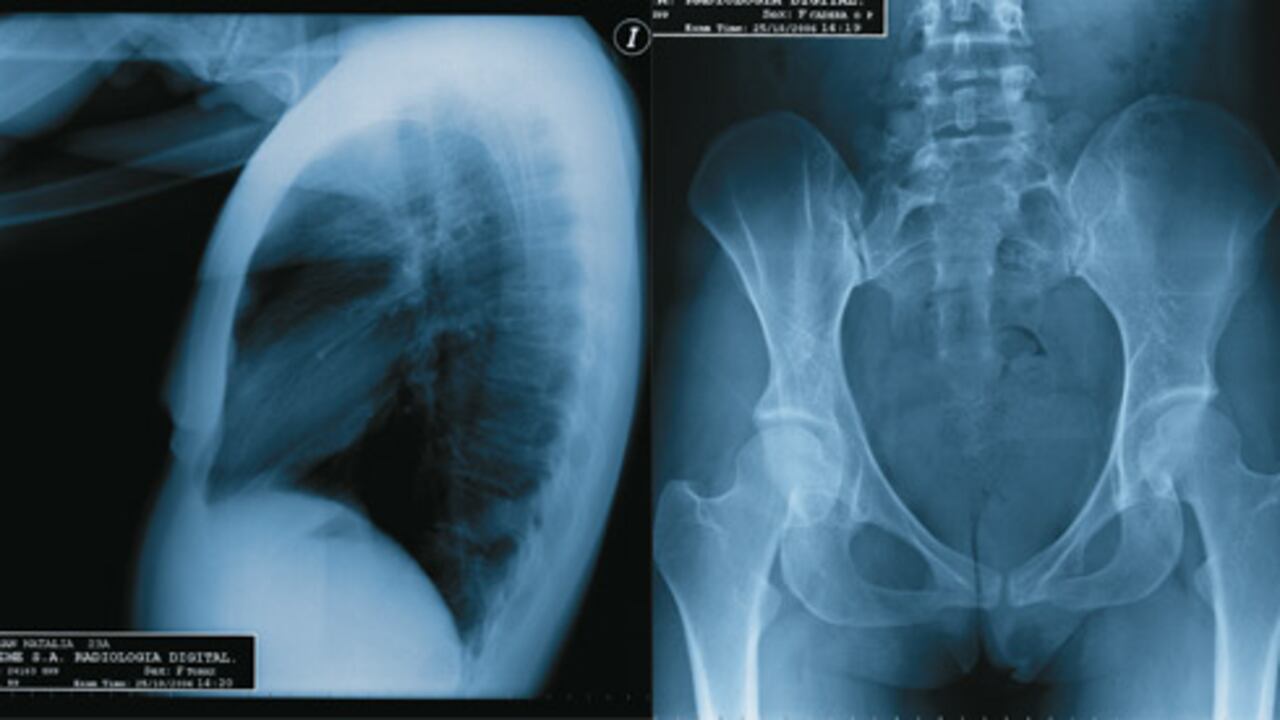

Ciento por ciento natural. La radiografía de tórax y de pelvis muestra unos índices de la estructura ósea normales. Los tejidos blandos y las líneas de grasa de la zona pélvica son sanos. Su estudio refleja que la cadera está dentro de los parámetros de sanidad.